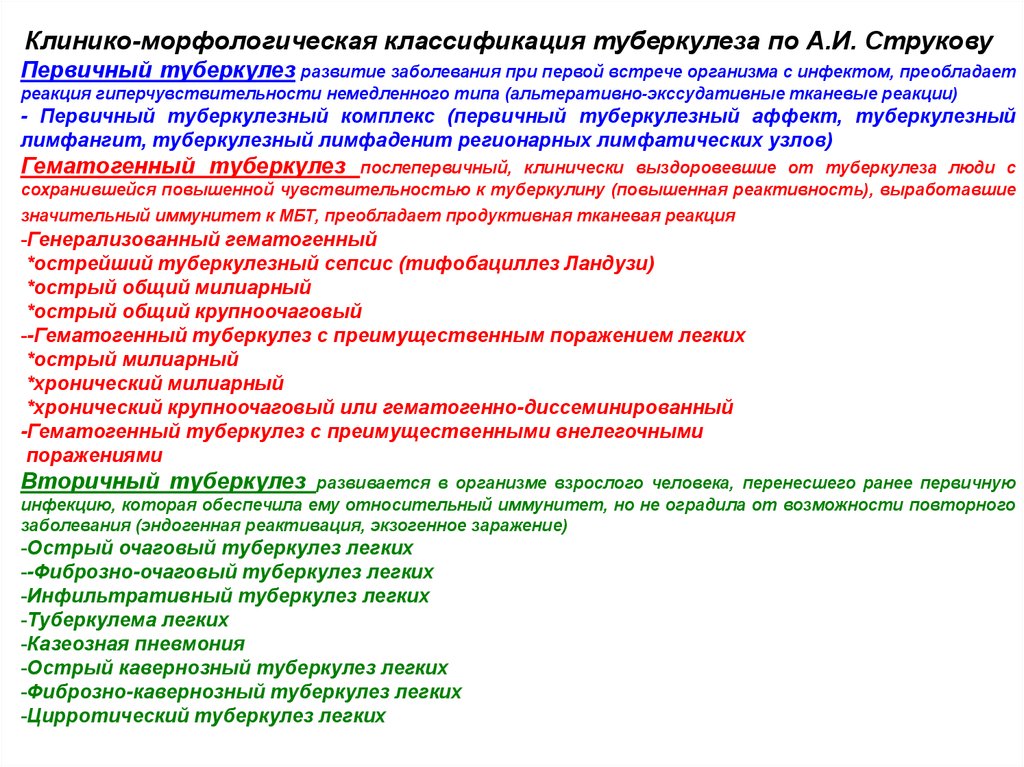

В клинической картине острого гематогенно диссеминированного туберкулеза преобладает